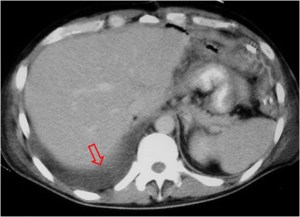

Este signo nos permite diferenciar entre derrame pleural y ascitis en un estudio de TC. Cuando existe una interfase nítida entre líquido y el hígado o el bazo, se trata de ascitis; cuando la interfase no es nítida, se trata de derrame pleural (flecha). El derrame pleural ocupa una posición más posterior y medial, mientras que la ascitis se localiza anterior y lateral al hígado y al bazo.

Esta segunda imagen corresponde a ascitis. Observa como la interfase entre el bazo y el líquido (flecha) es más nítida que en la imagen anterior. También lo es la interfase entre el hígado y el líquido.

SIGNO DEL ÁREA DESNUDA

Cuando en la TC vemos líquido en situación dorsal al hígado (flecha), éste se encuentra en la cavidad pleural, ya que el líquido intraperitoneal no puede acumularse en esta zona debido a que el peritoneo se repliega sobre la cúpula hepática sin llegar a cubrir la parte posterior del hígado, es decir, que no hay cavidad peritoneal por detrás del hígado y, por tanto, la ascitis no puede ocupar este espacio.

En esta imagen también está presente, lógicamente, el Signo de la interfase.

En la imagen correspondiente a ascitis que presentamos en el signo anterior, observa cómo se respeta la zona posteromedial del hígado.